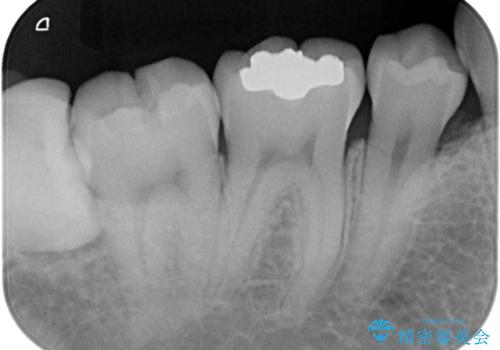

- 銀歯を外したいことを主訴に来院されました。

銀歯を丁寧に取り除き、形態を整えた上で、セラミックインレーで修復しました。

当院のセラミックインレーはe-max プレスインレーで製作しています。